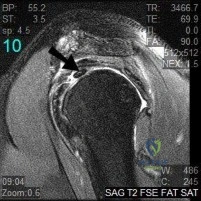

Question 2:

A 24-year-old athlete sustains a traction injury to the shoulder, presenting with weakness in forward elevation and isolated sensory loss over the lateral aspect of the proximal arm. An MRI reveals a compressive lesion within the quadrangular space. What anatomical structure forms the medial border of this space?

Options:

- Teres minor

- Teres major

- Surgical neck of the humerus

- Long head of the triceps

- Lateral head of the triceps

Correct Answer: Long head of the triceps

Explanation:

The quadrangular space transmits the axillary nerve and the posterior circumflex humeral artery. Its borders are: Superiorly - Teres minor; Inferiorly - Teres major; Medially - Long head of the triceps; Laterally - Surgical neck of the humerus. The patient's symptoms (deltoid weakness and lateral arm sensory loss) are classic for axillary nerve pathology.